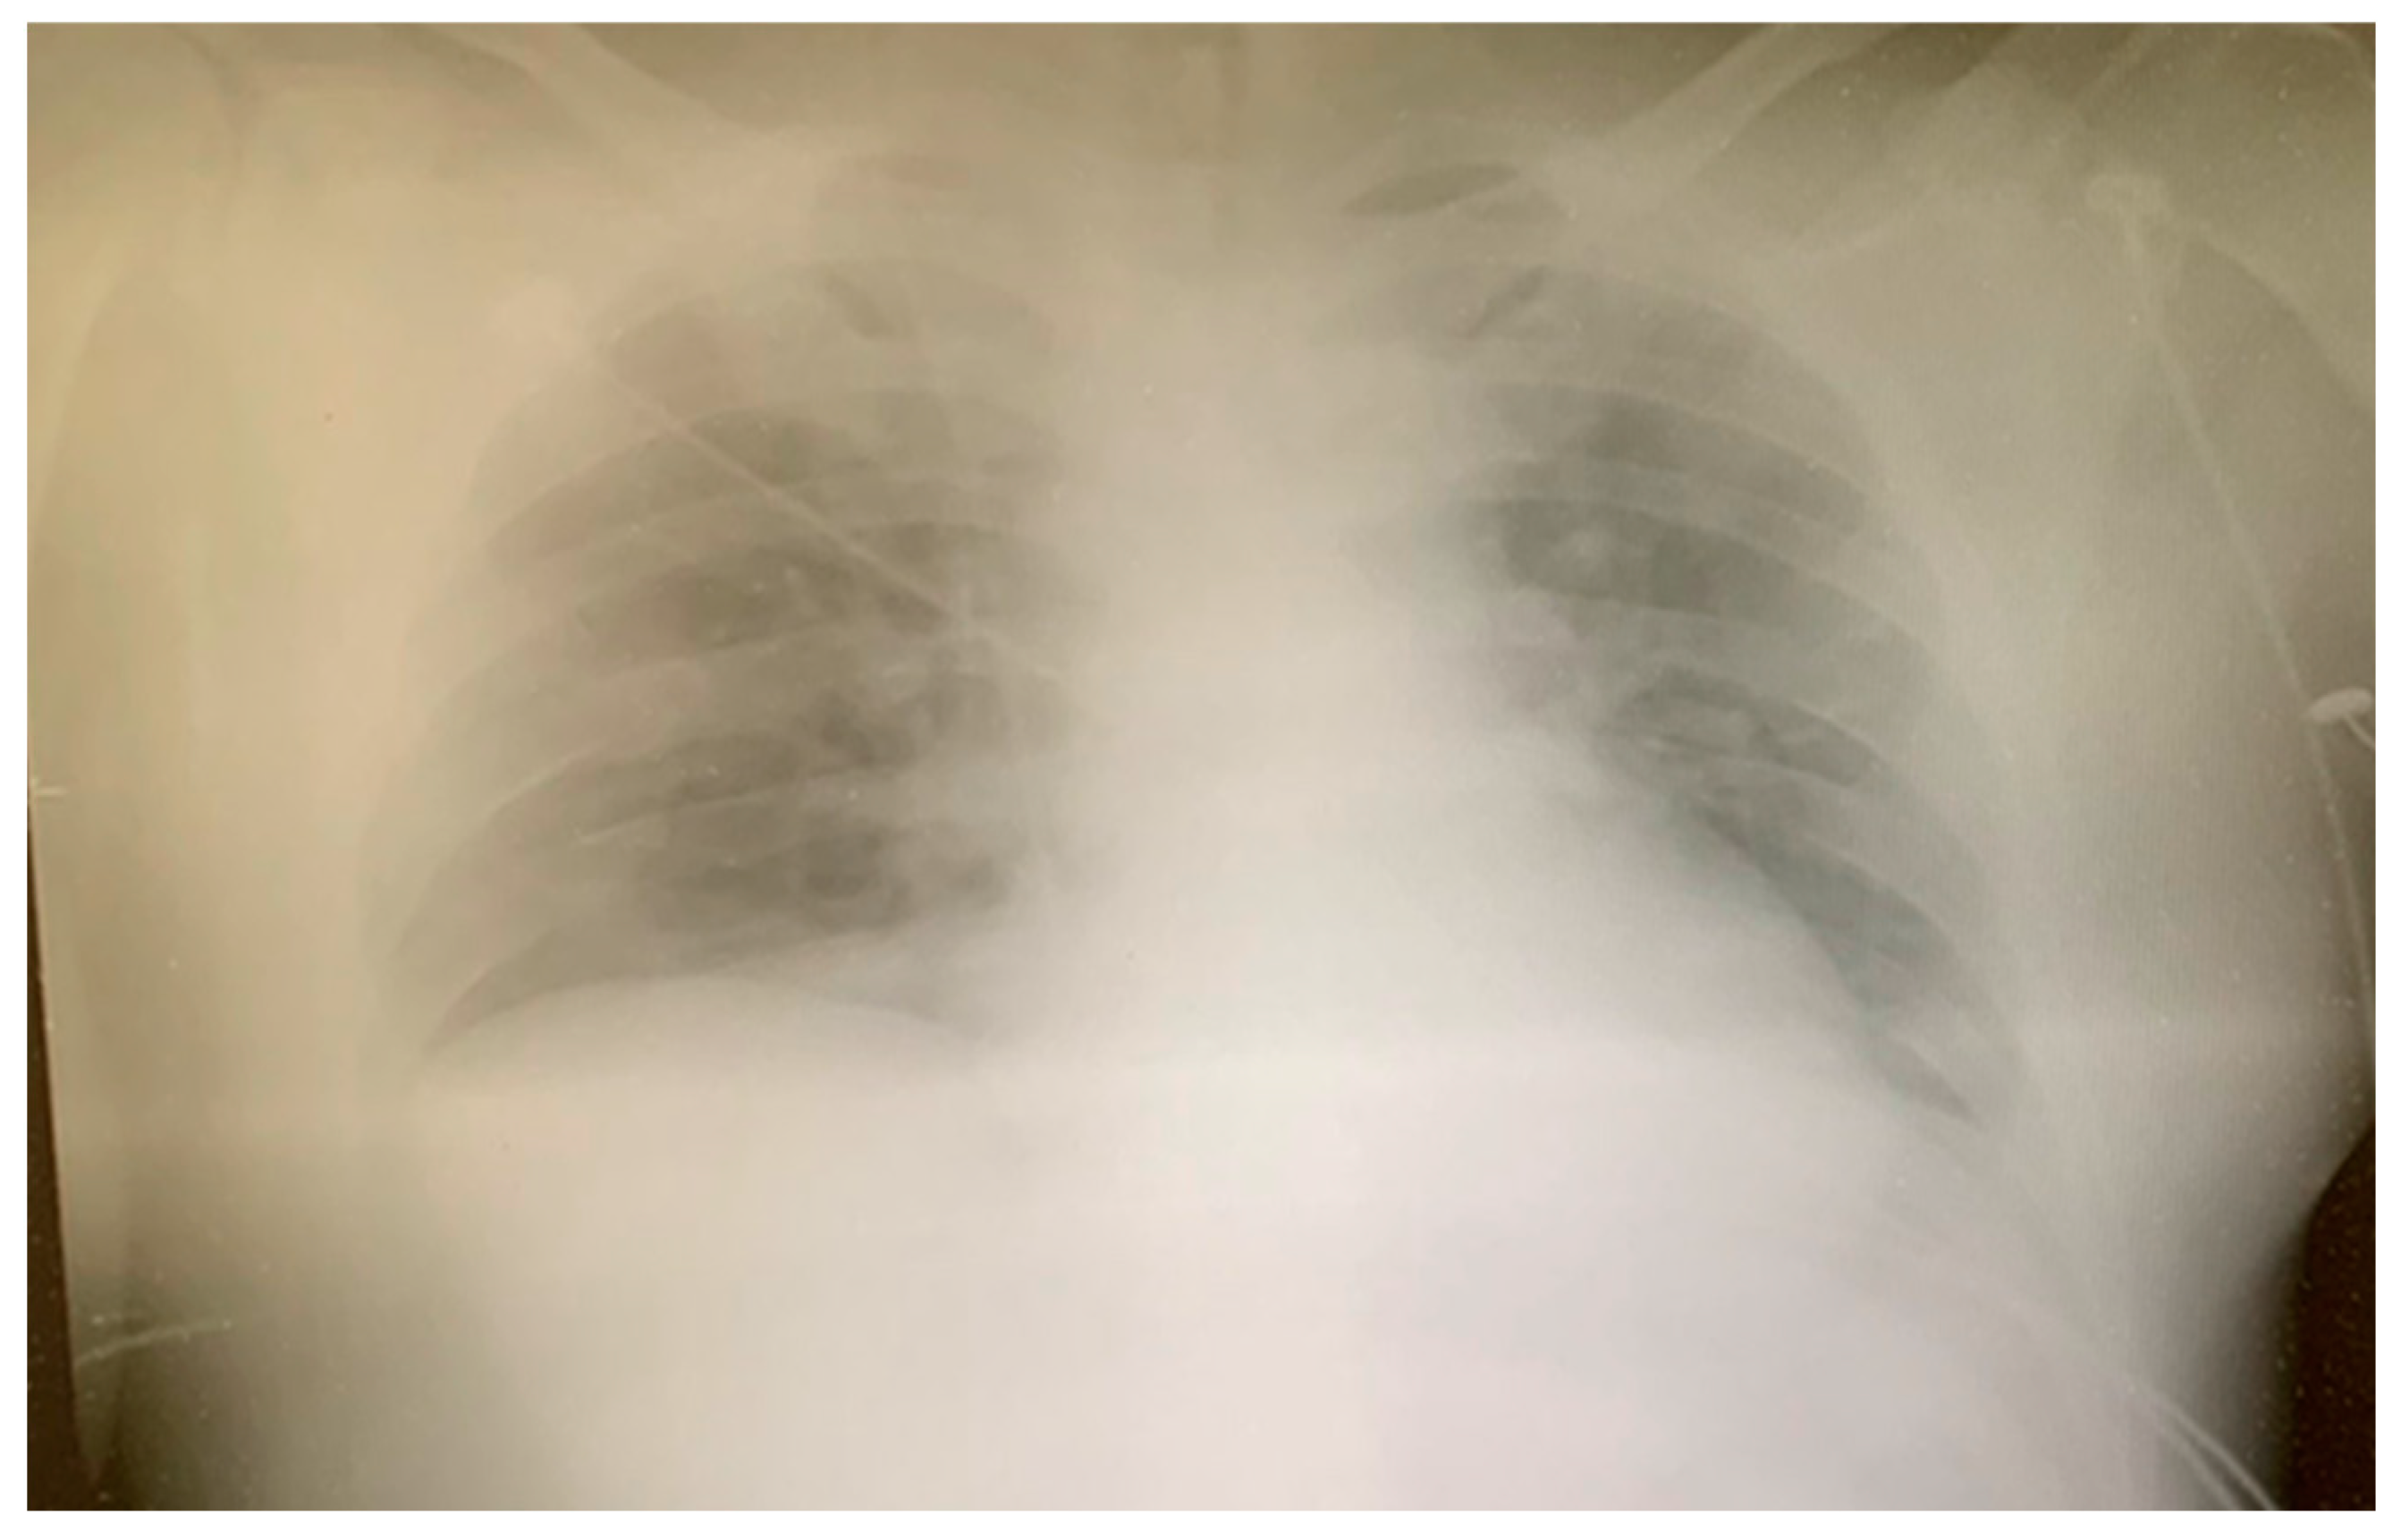

2. Case Report